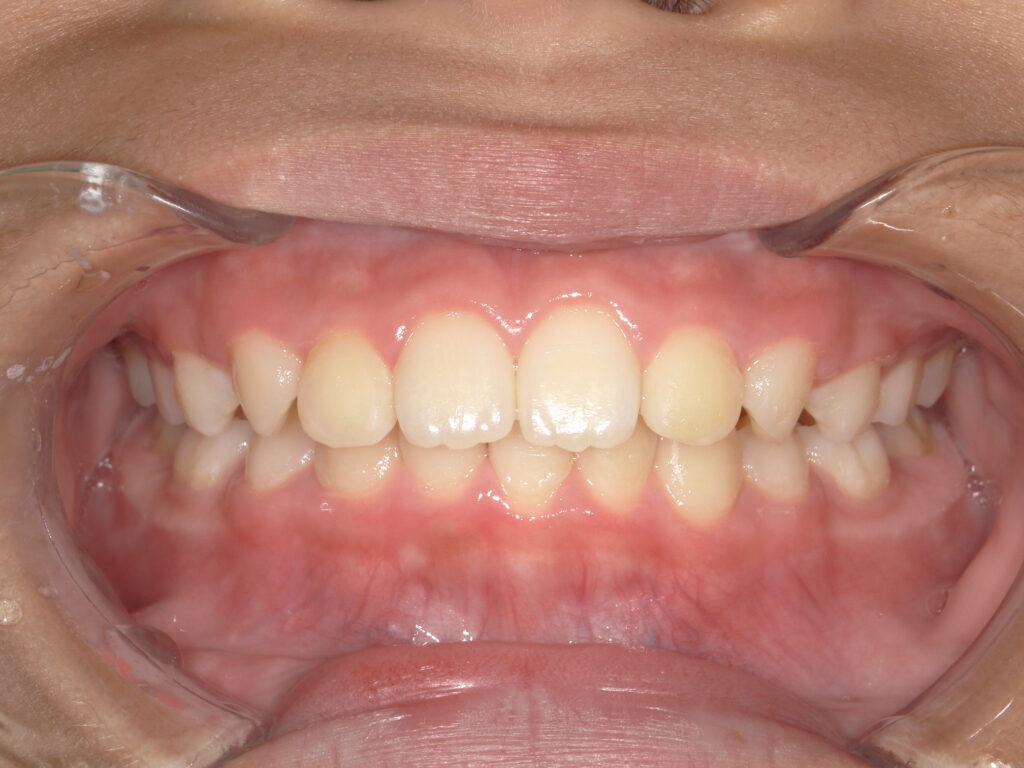

正面

治療後